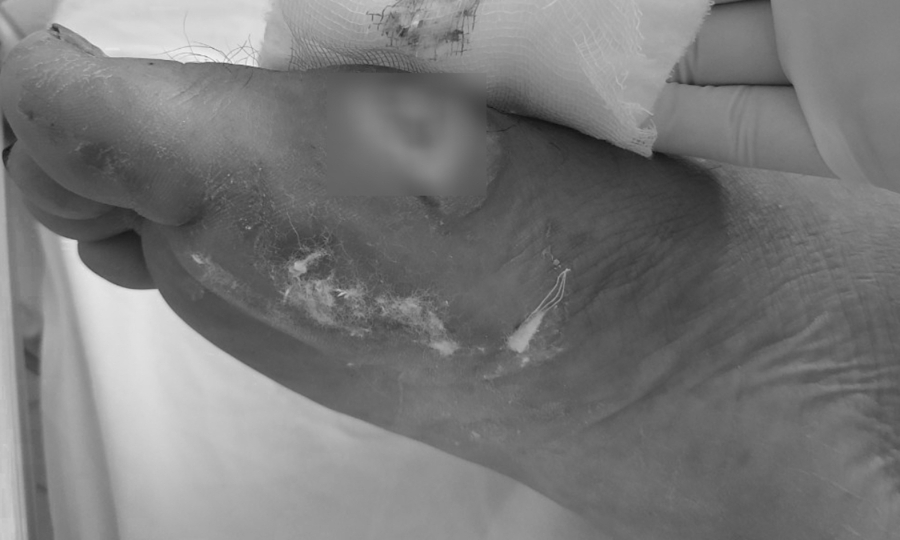

Chân bệnh nhân bị hoại tử do vi khuẩn Burkholderia. Ảnh: Bệnh viện cung cấp.

Sau đợt bão lũ kéo dài từ đầu tháng 10 đến nay, nhiều trường hợp mắc bệnh Whitmore đã gia tăng ở nhiều tỉnh miền Trung. Quảng Trị ghi nhận 24 ca, Bệnh viện Thừa Thiên-Huế tiếp nhận 30 ca … Bệnh viện Đà Nẵng điều trị 29 ca, bệnh nhân chủ yếu đến từ Quảng Nam, Nghệ An, Quảng Ngãi và Đà Nẵng. – Vết thương do áp xe do Whitmore gây ra đã được điều trị. Ảnh: Bệnh viện cung cấp.